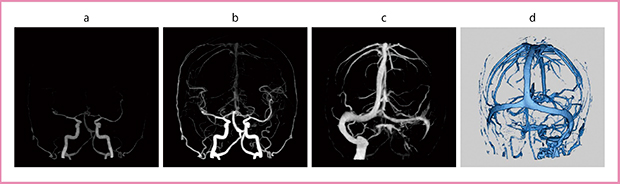

症例2は,一過性脳虚血発作(TIA)後に来院。MRIのT1,T2,FLAIRでは左内頸静脈に高信号が見られるが,flow in effectの可能性があり,これだけで血栓と確定することはできない。この症例では,MRAで動脈には狭窄を認めず,左内頸静脈と海綿静脈洞から上錐体静脈洞に高信号が見られた(図5)。MRAで静脈が描出される場合には静脈逆流の可能性が多いと言われており,実際に多くの症例を経験するが,その中に無症候性静脈血栓症が含まれていることも少なくない。4D-CTAでは動脈相には異常がなく,静脈相では左横静脈洞の描出が悪く,S状洞から下は描出されず,静脈洞血栓症と診断された(図6)。

図6 症例2の4D-CTA

a,b:動脈相 c:静脈相 d:静脈相のVR画像